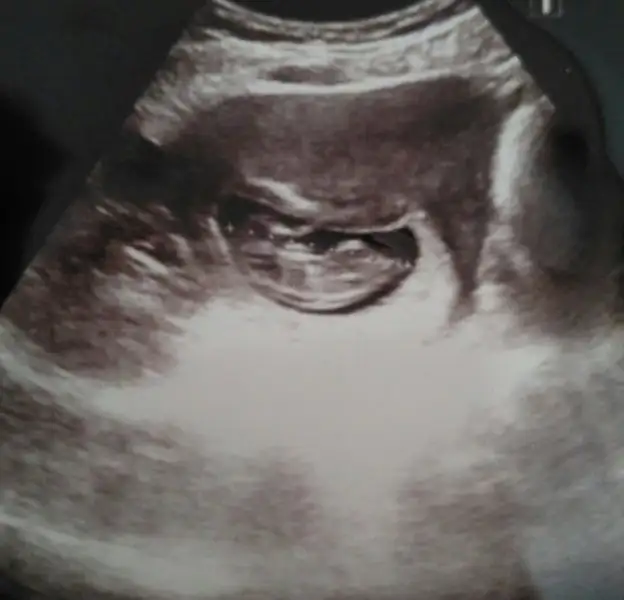

Seninki kiz benceArkadaslar benim bebeğim 7+3 haftasında ortada duruyor sizce cinsiyeti nedir?? Tahminde bulunursanız sevinirim

Kizlar banada bi yorum yapin lutfen yaa. Resimde 10 haftalik. Cok merk ediyorum

Erkege benziyor canimKizlar banada bi yorum yapin lutfen yaa. Resimde 10 haftalik. Cok merk ediyorum